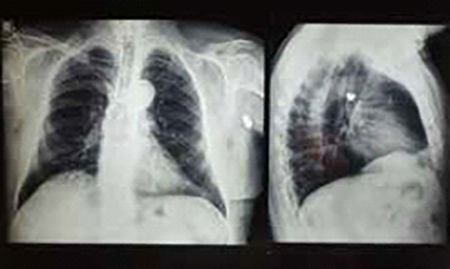

F.F.M. Masculino de 72 años de edad. A diferencia del caso precedente el paciente concurre a la consulta por motivos refractivos, y en el interrogatorio sobre antecedentes oftalmológicos relata que 15 años antes perdió la visión de su OD a raíz de un intento de robo por parte de dos masculinos los que lo sorprenden subiendo a su rodado obligándolo a marcharse con ellos con el mismo. Ante su ansiedad y al querer resistirse uno de los malvivientes le efectúa un disparo a unos 50 cm. de distancia el que ingresa por piel de párpado inferior OD ángulo ínfero-interno, y luego de un curioso recorrido intracorporal termina alojándose en la axila izquierda, en una trayectoria que Bonnet describe como proyectiles migradores 2 lesionando en su camino órbita y globo ocular derecho y parcialmente el plexo braquial izquierdo. A consecuencia de los mismos el paciente tiene ausencia de visión OD, anestesia en el territorio inervado por la segunda rama del trigémino derecho, e impotencia funcional para elevar el miembro superior izquierdo. El paciente refiere que hubo desprendimiento retinal que fue operado poco tiempo después del incidente. Cinco años después se lo operó por catarata traumática.

• Fondo de ojo: OD extensa área de denudación coriorretinal, atrofia óptica, gran movilización de pigmento.

• OI sin particularidades (Figuras 5 y 6)

Figura 6: radiografía de craneo, tomografía computada, radiografía de tórax frente y perfil.